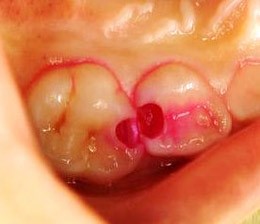

う蝕検知液は、虫歯の部分だけを赤く染め出す薬液です。使用することで削るべき部位が一目で分かるため、歯を削る量を最小限に抑えられます

右の写真をご覧ください。通常、ここまで虫歯が進行すると、多くの歯科医院は抜歯を選択すると思います。しかし、京都駅前パール歯科は違います。可能な限り歯を残すため、ケースによって「エクストリュージョン法」という治療法を行っています。

エクストリュージョン法は、歯茎に埋まっている自分の歯根を引っ張り出し、そこを被せ物の土台とし、抜歯を回避する治療法です。自分の歯を活かして被せ物ができるため、天然歯を残したいという方にお勧めの治療法です。(自費治療になります。)